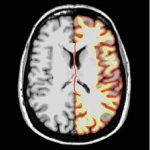

Naučnici Univerziteta u Cirihu, ustanovili su da sklonost ka altruizmu zavisi od količine sive materije u mozgu.

Naučnici Univerziteta u Cirihu, ustanovili su da sklonost ka altruizmu zavisi od količine sive materije u mozgu.

Ispostavilo se da je kod onih, kod kojih u prostoru između parijetalnog i temporalnog režnja mozga ima više sive mase, veća verovatnoća da će podelili novac sa nepoznatom osobom.

Istraživači su otkrili da je kod cicija aktivnost u tom delu mozga veoma intenzivna čim se i najmanja količina novca nađe u igri, dok se kod altruista to područje aktivira samo kada je reč o velikim svotama.

Ciriški naučnici su, takođe, ustanovili da postoji razlika u količini sive materije, te da je kod škrtica ona manja nego kod darežljivih osoba.